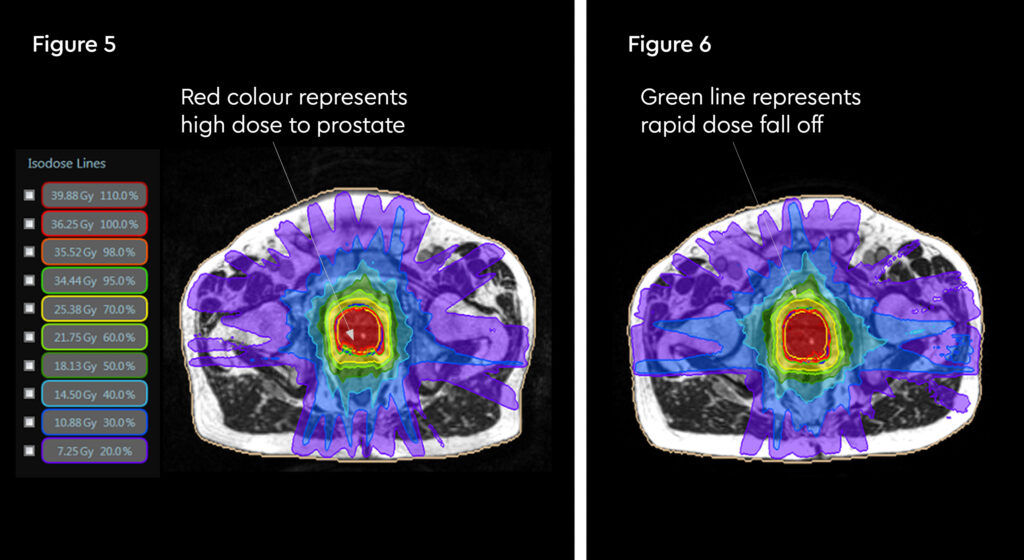

At each session, daily adaptation was performed to account for changes in the position of the prostate and for variable bladder and bowel filling. Figure 1 and figure 2 illustrate the typical differences seen between the original planning MRIdian scan and that seen on the day of treatment due to day-to-day organ movement. Figure 3 and figure 4 illustrate how these movements were accommodated with the on-table plan adaptation.

Fig 3: Prostate SABR delivery plan. Prostate volume covered by 95% isodose (green line, red arrow). Tight conformality at rectal/prostate boundary (white arrow), and rapid drop off of high dose (50% isodose, green line, green arrow) to optimise dose delivery to the prostate and limit dose to the rectum, reducing the risk of toxicity

Fig 4: Fraction 3, adapted plan, optimised for anatomy of the day. Prostate volume covered by 95% isodose (green line, red arrow). Tight conformality at rectal/prostate boundary (white arrow), and rapid drop off of high dose (50% isodose, green line, green arrow) to optimise dose delivery to the prostate and limit dose to the rectum, reducing the risk of toxicity

Fig 5: Radiotherapy plan

Fig 6: Plan adaptation. Tight conformality at rectal and prostate boundary is demonstrated by the arrow. Rapid reduction of high dose optimises dose delivery to the prostate and limit dose to the rectum, reducing the risk of long term toxicity.